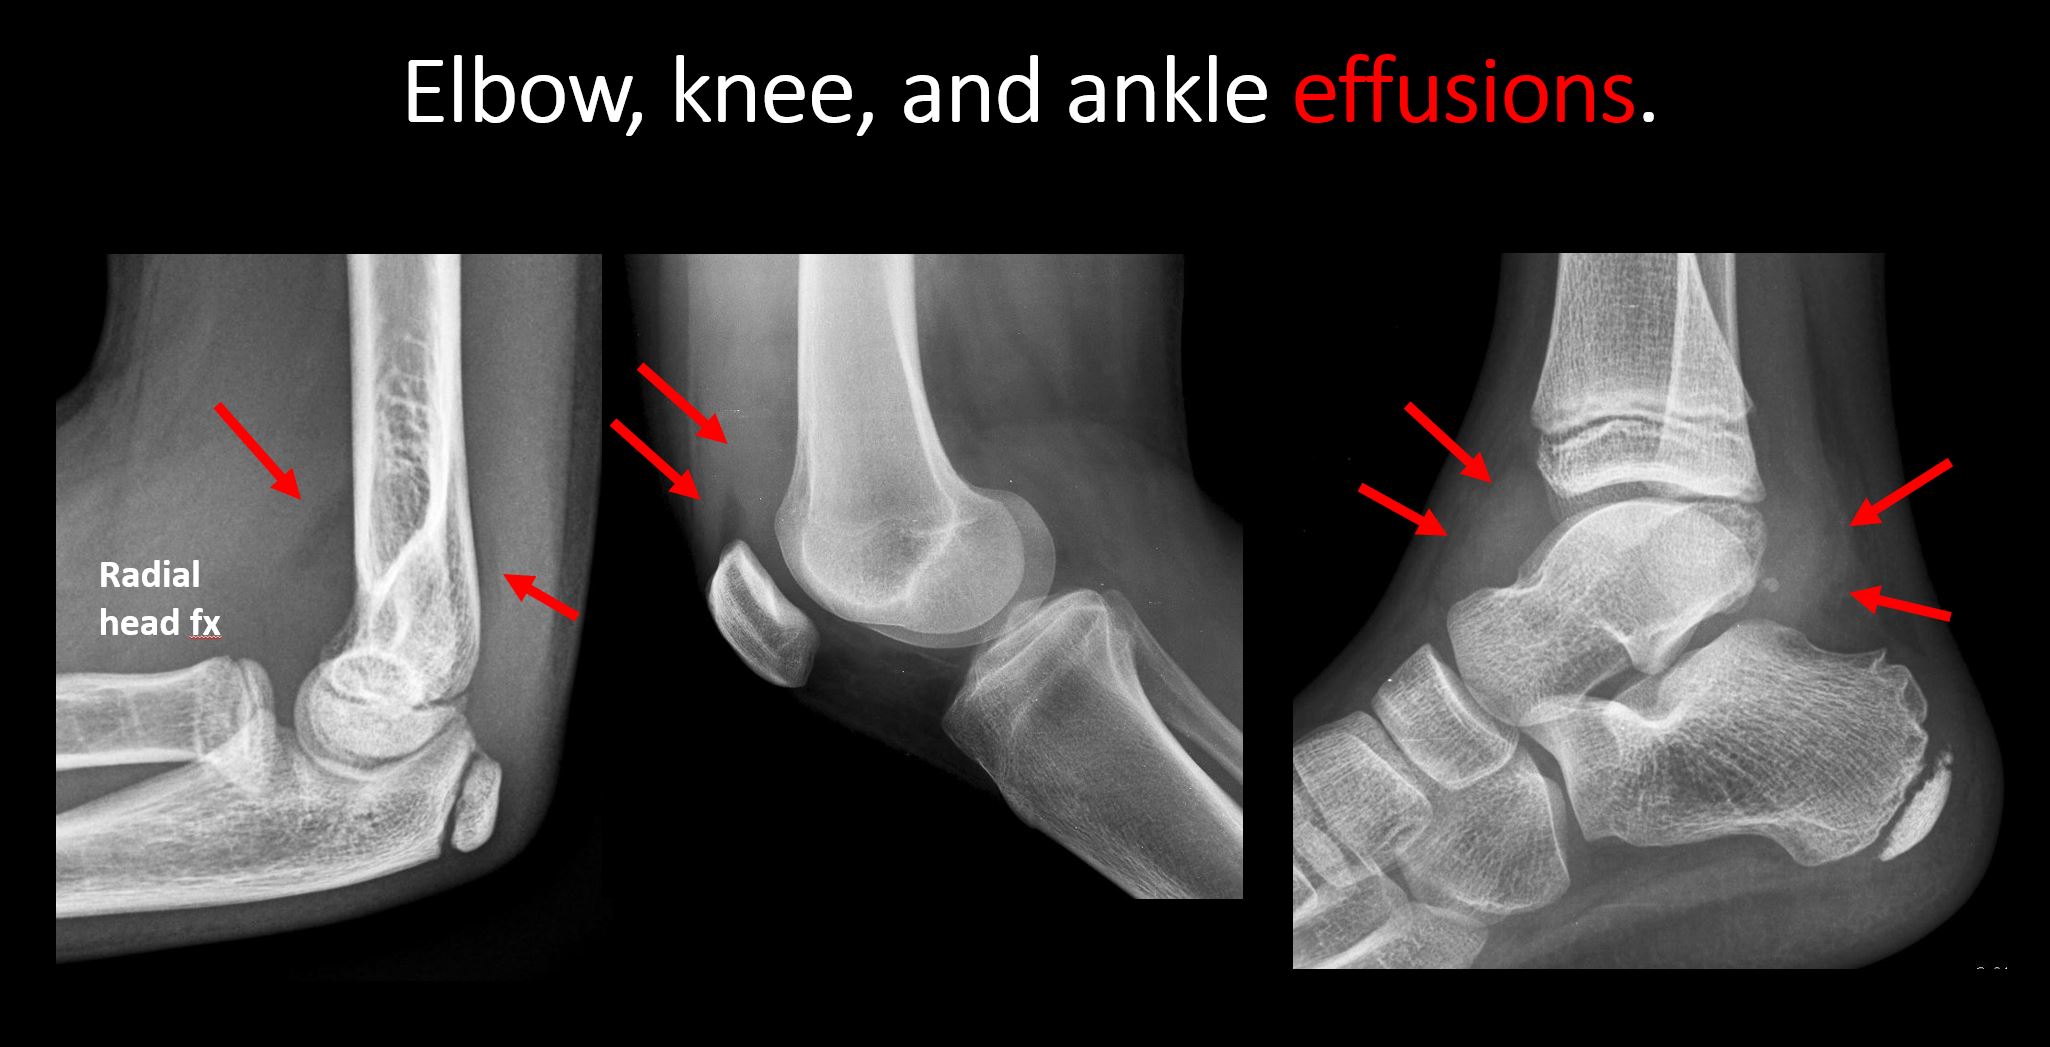

There is an effusion, fat pad displacement, or fat fluid level. [Yes/No]